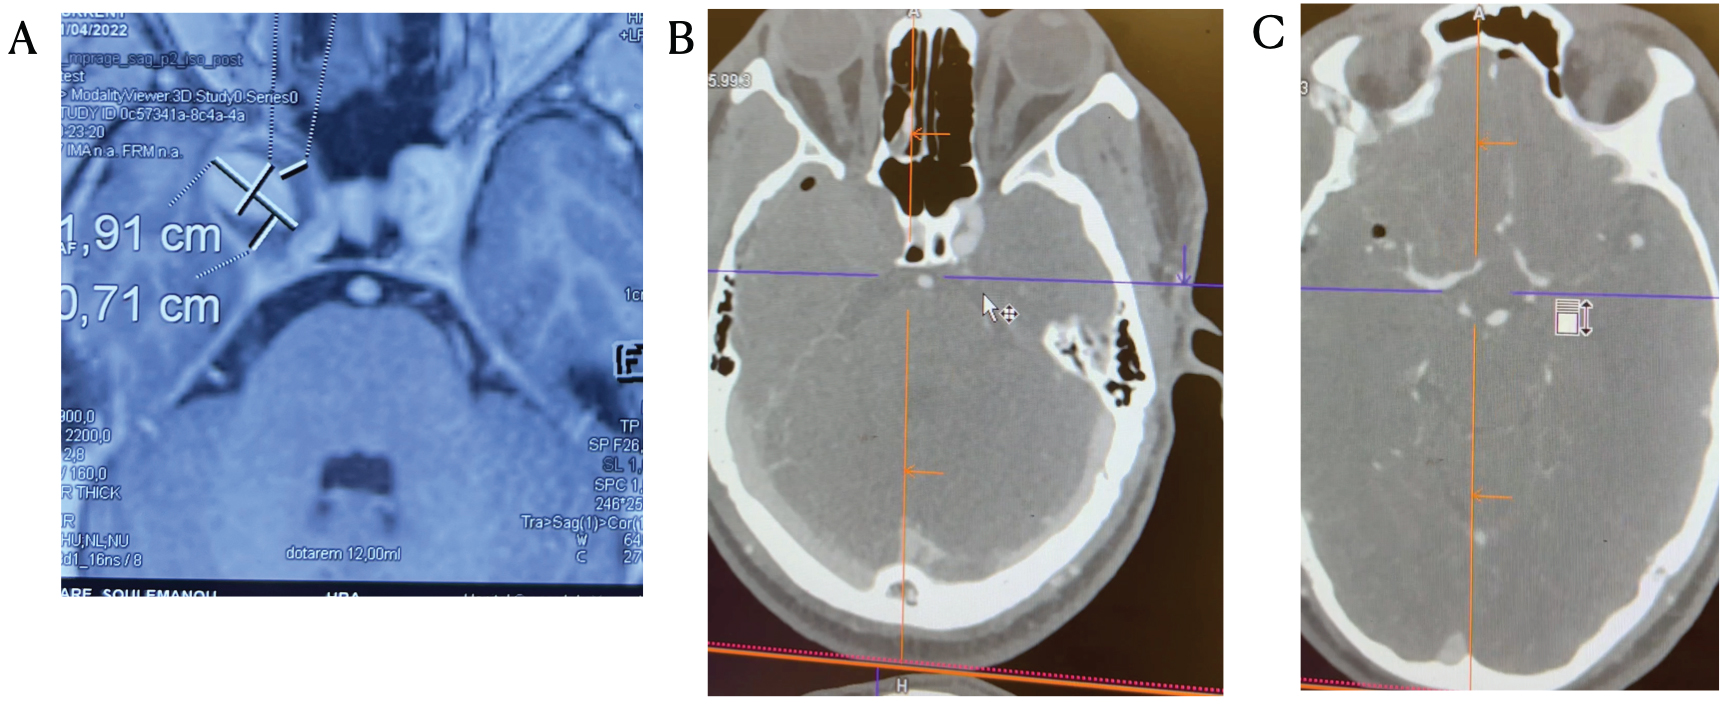

The first case is a 32-years-old male patient presented to the outpatient clinic 2 months before surgery with progressive diplopia. A partially thrombosed 2 cm aneurysm of the right ICA was identified (Figure 1a). Through a pterional craniotomy the ICA on the right side was inspected and dissected under general anesthesia (Video 1). The aneurysm was extraduraly and was pushing the dura upwards. The ICA immediately proximal to the ophthalmic artery was ectatic. After dissecting the ICA we applied a temporary clip distal of the ophthalmic artery and inspected the ICA filing distal of the clip. No vascular collapse could be seen. Still we decided against an ICA occlusion and planed the occlusion in a second, awake surgery. The patient was informed about the second surgery, which would be in a fully awake state and consented. In the second surgery following 3 days after the first, the already dissected ICA, was approached (under local anesthesia and no sedation) and clip-occlusion was performed between the ophthalmic and pcom arteries (Video 2). The ophthalmic artery was occluded with a second clip to exclude aneurysm filling from the ECA circulation. Immediately after the clip application the patient was asked to move his left and right extremities every 60 seconds until the wound was closed (Video 3). We also asked him of any changes of his sight. After skin-closure the patient stayed one night in the ICU and after cCT and CTA he was transported to the ward and was discharged 5 days after occlusion. The double vision persisted, but as could be seen in the CTA (Figure 1b) the aneurysm and the ICA proximal to the clip were completely thrombosed. Distal to the clip a regular, ICA flow could be seen (Figure 1c).

Figure 1: (A) Right ICA aneurysm of the cavernous sinus causing diplopia; (B) Postoperative CTA showing a completely thrombosed aneurysm and ICA on the right side; (C) The ICA and intracerebral circulation distal of the clip is completely intact as can be seen on the MCA and ACA the right side. View Figure 1